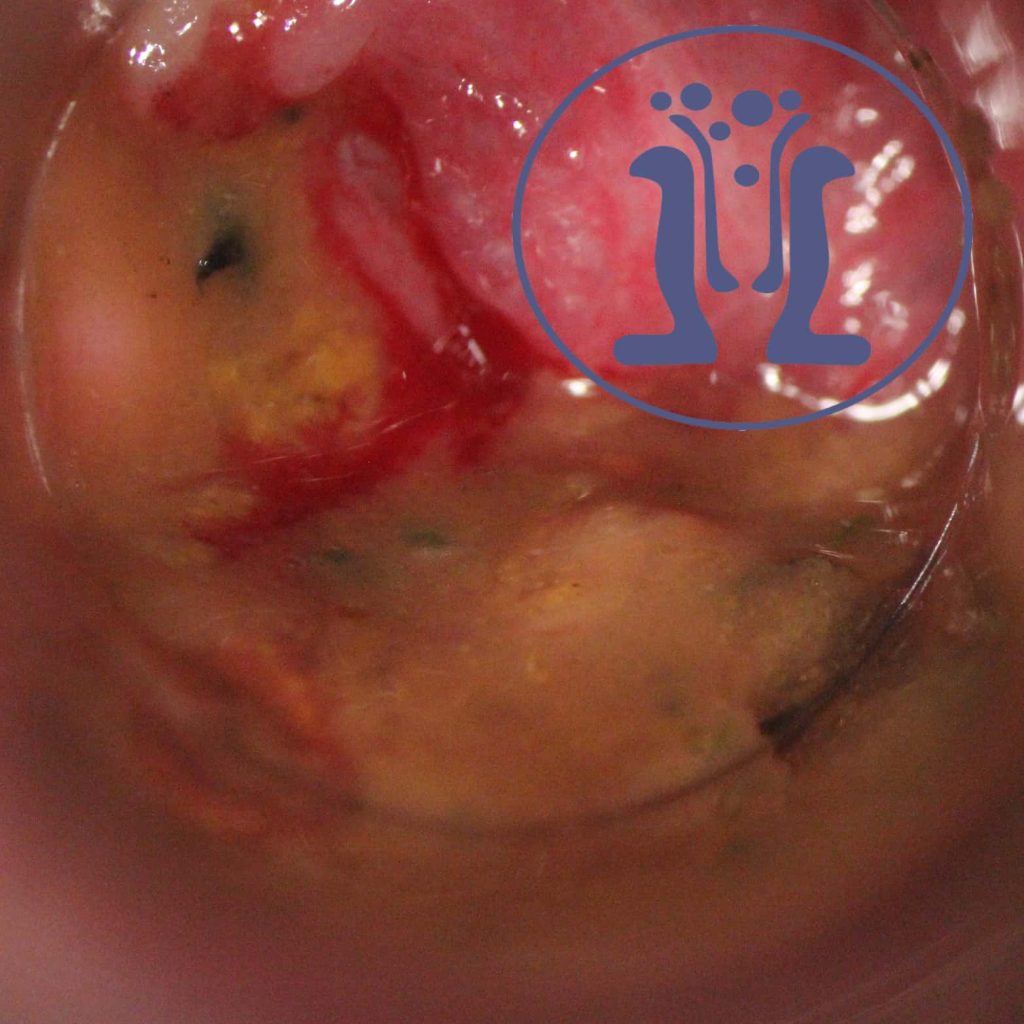

Γυανίκα σε ηλικία γύρω στα 40 χρόνια ταλαιπωρείται με ενδείξεις φλεγμονής, πυρετό, καταβολή και κακοδιαθεσία. Εχει συμπτώματα από τον πρωκτό εδώ και πέντε χρόνια. Εχει χειρουργηθεί δυο φορές για περιεδρικό απόστημα και έχει κάνει και μαγνητικές τομογραφίες. Η κατάσταση της διευκρινίσθηκε πλήρως με την χαρτογράφηση που έγινε στο «Χειρουργικό Ιατρείο Πρωκτού». Εχει μία μεγάλη κοιλότητα πίσω από τον πρωκτό που επικοινωνεί με τον αυλό του πρωκτού. Στον πρωκτό ανευρέθηκε άφθονο πύον. Για τον λόγο αυτό η κοιλότητα περιέχει μεγάλη ποσότητα πύου. Η ασθενής πρέπει να χειρουργηθεί σε πολλές δόσεις για να θεραπευθεί χωρίς τραυματισμό των σφιγκτήρων και επακόλουθη ακράτεια.